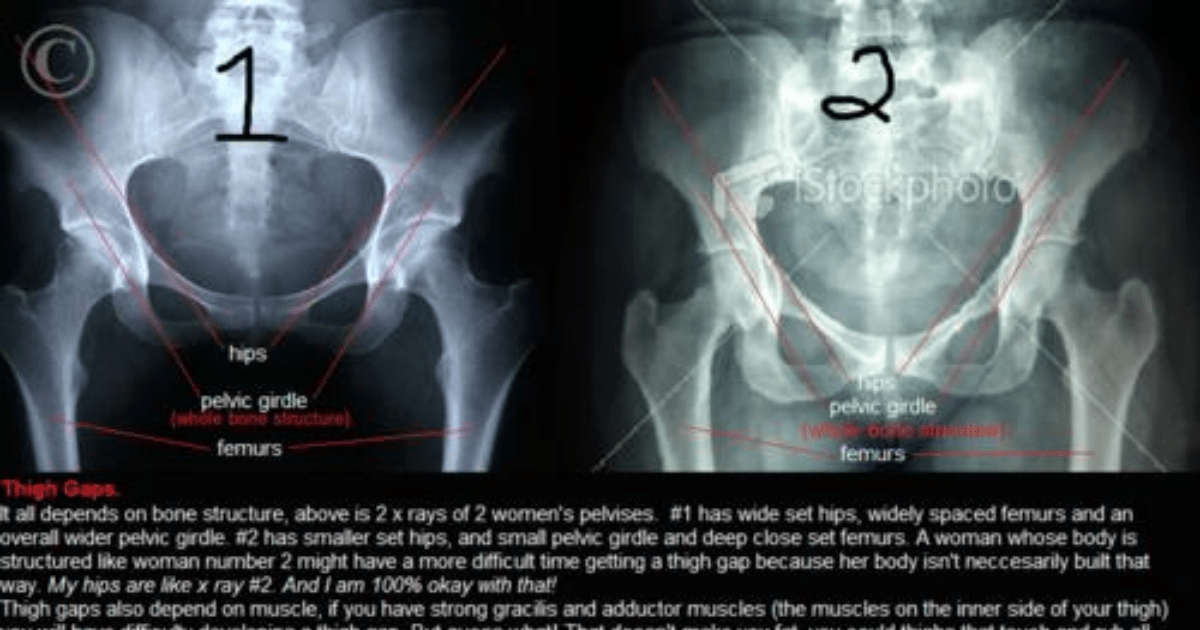

The human body has more than 200 bones. Thigh Gap Is All About Bone Structure Girlsaskguys

Keep in mind, however, that the . ١٠ جمادى الأولى ١٤٤٣ هـ. Keep in mind, however, that the term . These bones do everything from protecting vital organs to giving muscles and nerves an anchor. The bones of the body come. Bones that are longer than they are wide are called long bones. Irregular bones vary in shape and structure and therefore do not fit into . Part of a long bone of a large ungulate.